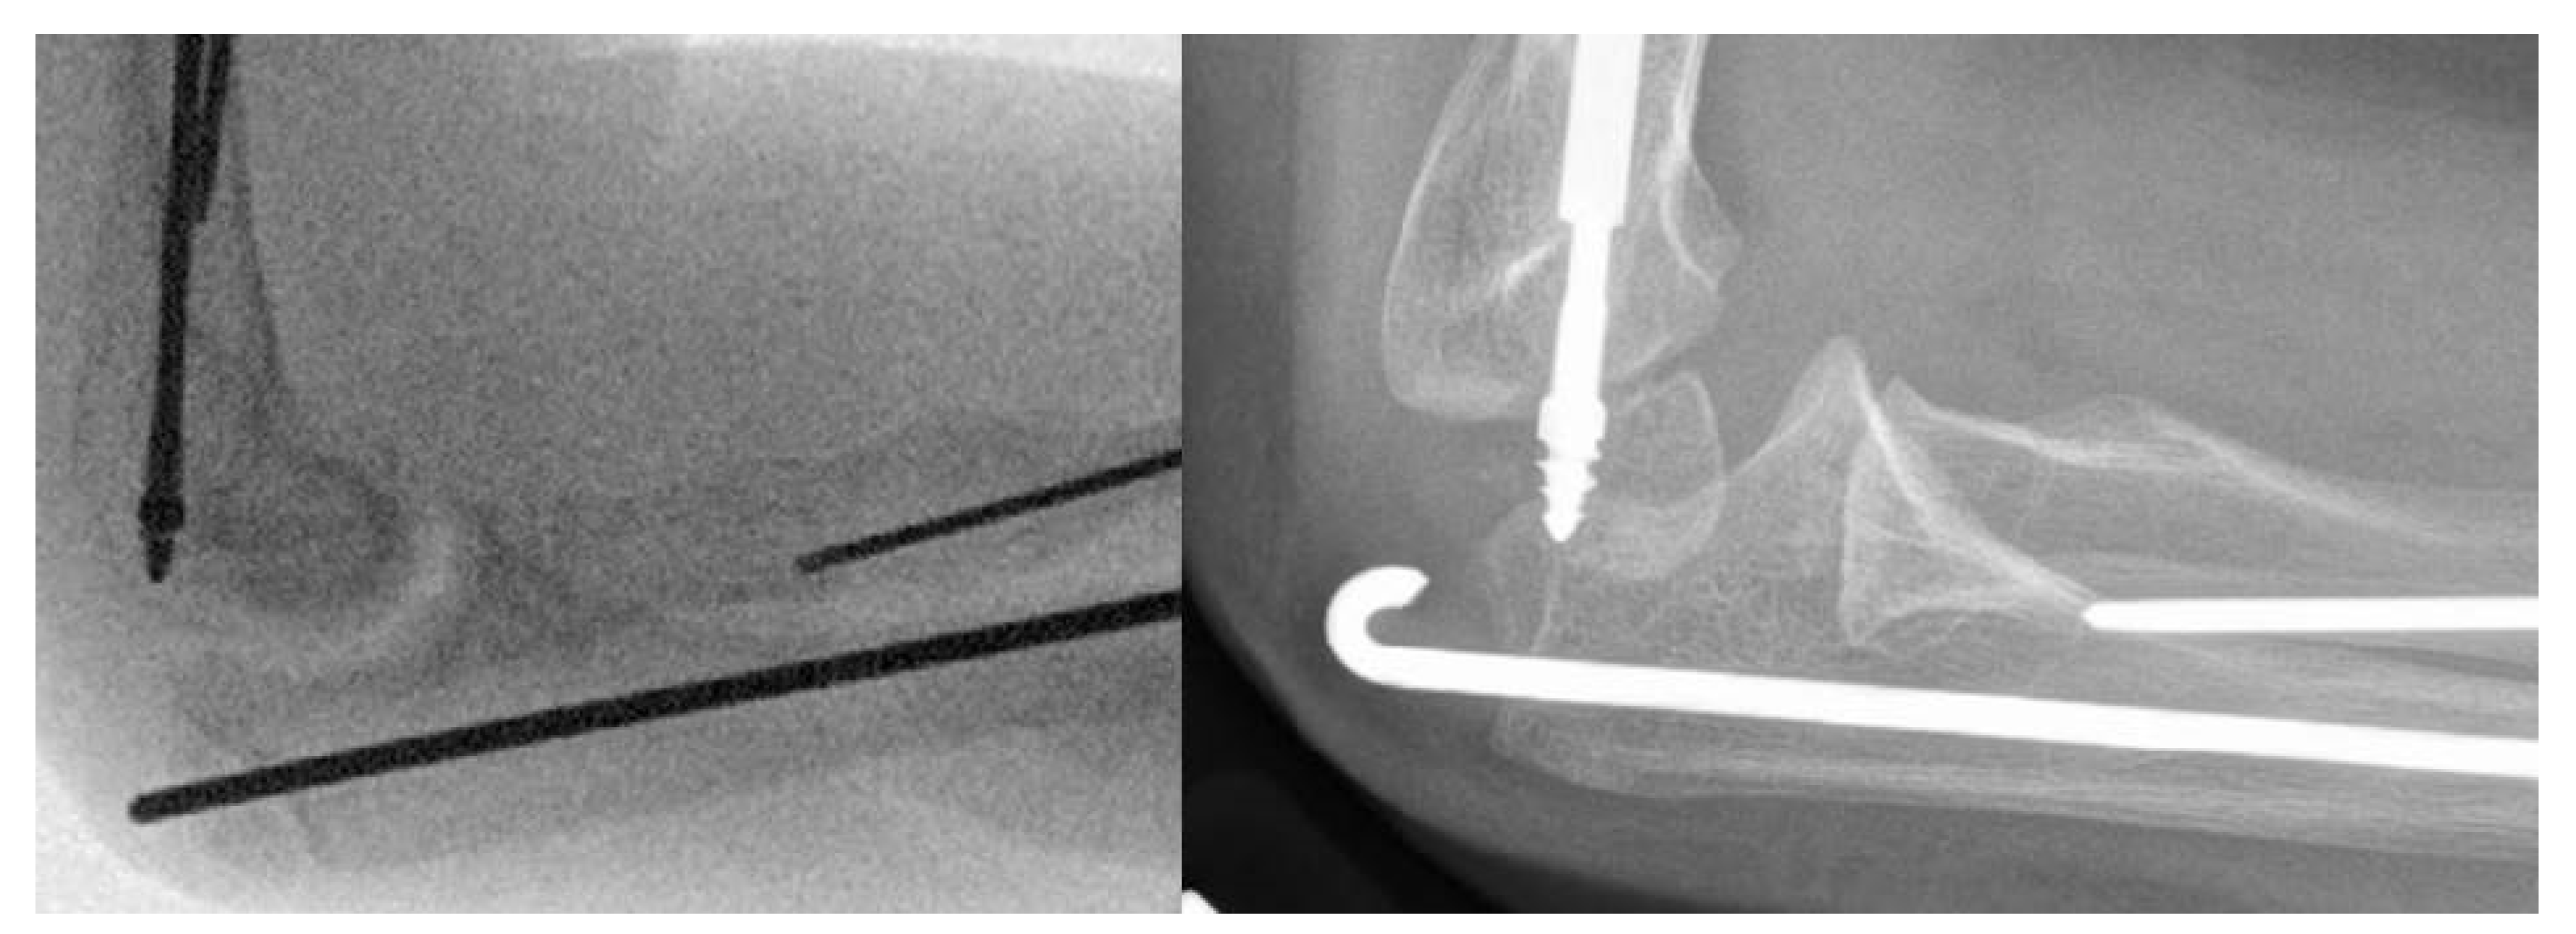

We have attempted to decrease the frequency of wire migration by bending the tip of the ulnar wire into a shepherd’s crook and/or keeping the wire straight and fully tamping it into the cartilage of the olecranon (Figure 3). For the radial wire, we have had a special tamp fashioned (Figure 4) that fits the end of the 0.062” k-wire and confirm both radiographically and under direct vision that the wire is completely buried in the cartilage of the radial styloid. Our current cohort of patients is not large enough and has not been followed long enough to determine if these changes have decreased our wire prominence problems, longer-term follow-up will help to determine this.

Figure 4. Tamp utilized to bury the k-wire into the cartilage of the olecranon apophysis or the distal radial styloid cartilage.